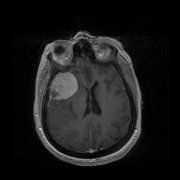

前中颅窝底包括哪些部位?前中颅窝底脑膜瘤严重吗?

脑膜瘤一文详解:分级、良恶性、严重程序及诊疗手术费用相关